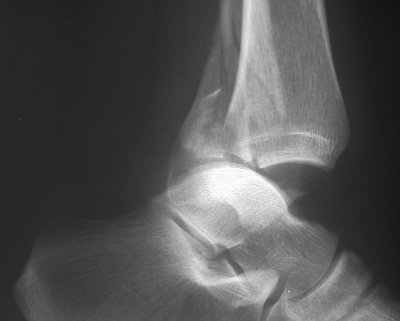

- Click on the image for a larger versionBLateral radiograph of the ankle. This shows the fracture of the posterior malleolus.